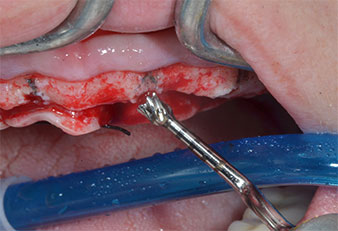

A flame-shaped, diamond-coated piezoelectric instrument (Piezomed I1) was used to mark the implant positions and to perform pilot preparation (Fig. 3). Care was taken to use an up and down movement, with reduced power, full irrigation and low pressure (below 300 g). Next a pilot instrument (Piezomed I2A/I2P) was applied for the initial 2 mm diameter enlargement of the implant sites (Fig. 4), followed by a 3 mm insert (Fig. 5).

In the present case the Z25P and Z35P instruments were not used due to the relatively soft posterior bone, which was easily managed with the I3A/I3P.

Due to the relatively hard bone (D2) in this area, the 10 mm long implant sites at positions 11 and 21 were finalized with a 4 mm diameter rotary drill, in combination with a W&H WS-75 L surgical contra-angle handpiece, the W&H Implantmed implant motor and the optional W&H Osstell ISQ module. In contrast, due to the soft bone the posterior sites were prepared to a final 3 mm diameter using the Piezomed I3P instrument. The implants were finally placed transgingivally to osseointegrate for three months (Figs. 6-10). The existing denture was retained on four provisional implants (Fig. 8).